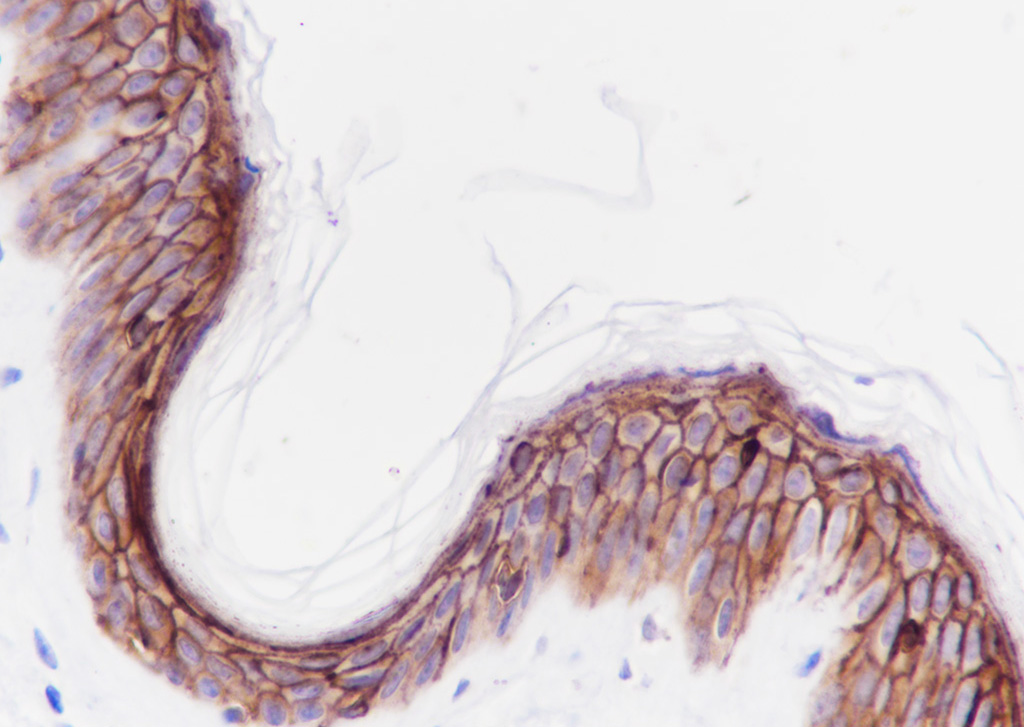

Tissue: Human skin Section type: Formalin fixed & Paraffin -embedded section Retrieval method: High temperature and high pressure Retrieval buffer: Tris/EDTA buffer, pH 9.0 Primary ab dilution: 1:1000 Primary ab incubation condition: 1 hour at room temperature Counter stain: Hematoxylin Comment: Color brown is the positive signal for bsm-60286R

Tissue: Human esophagus Section type: Formalin fixed & Paraffin -embedded section Retrieval method: High temperature and high pressure Retrieval buffer: Tris/EDTA buffer, pH 9.0 Primary ab dilution: 1:1000 Primary ab incubation condition: 1 hour at room temperature Counter stain: Hematoxylin Comment: Color brown is the positive signal for bsm-60286R

Tissue: Human tonsil Section type: Formalin fixed & Paraffin -embedded section Retrieval method: High temperature and high pressure Retrieval buffer: Tris/EDTA buffer, pH 9.0 Primary ab dilution: 1:1000 Primary ab incubation condition: 1 hour at room temperature Counter stain: Hematoxylin Comment: Color brown is the positive signal for bsm-60286R